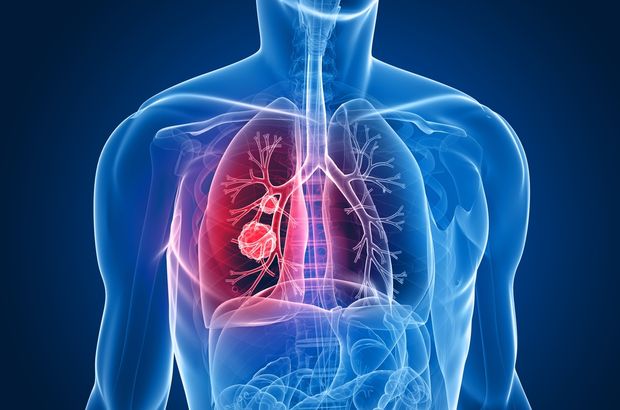

Akciğer vücudumuzun oksijen gereksinimini sağlayan organımızdır. Her organ gibi akciğerimiz de birçok hücreden oluşur. Bu hücreler akciğerin normal olarak görevini yapabilmesi için ihtiyaç doğrultusunda bölünerek çoğalırlar. Akciğer kanseri, yapısal olarak normal akciğer dokusundan olan hücrelerin ihtiyaç ve kontrol dışı çoğalarak akciğer içinde bir kitle (tümör) oluşturmasıdır. Burada oluşan kitle öncelikle bulunduğu ortamda büyür, daha ileriki aşamalarda ise çevre dokulara veya dolaşım yoluyla uzak oranlara yayılarak (karaciğer, kemik,beyin vb. gibi) hasara yol açarlar. Bu yayılmaya metastaz adı verilir.